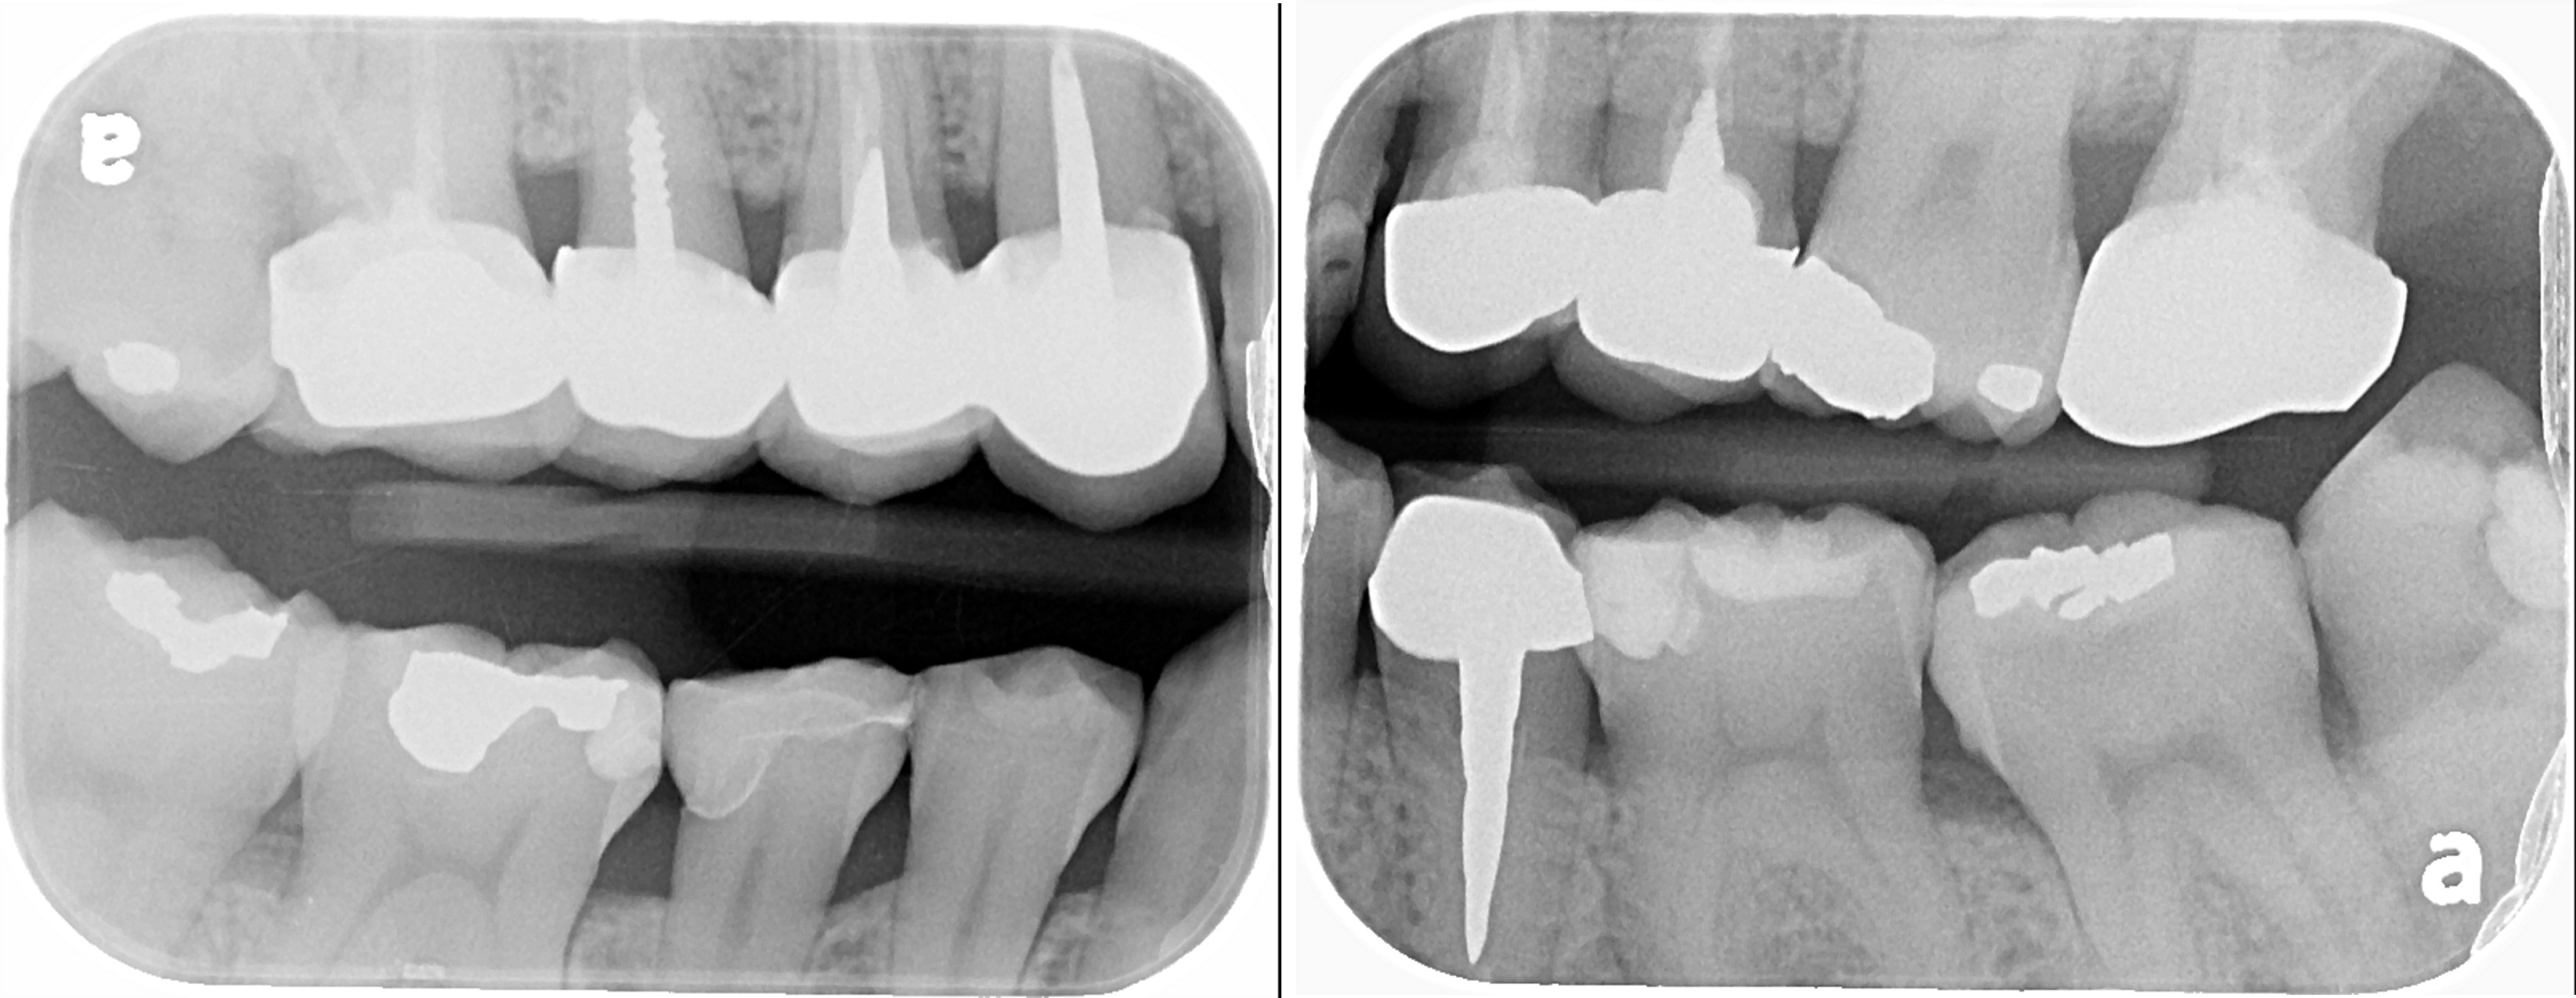

治療前,大臼齒冷熱敏感

X光可見大臼齒內有蛀洞

治療後,X光密合度良好